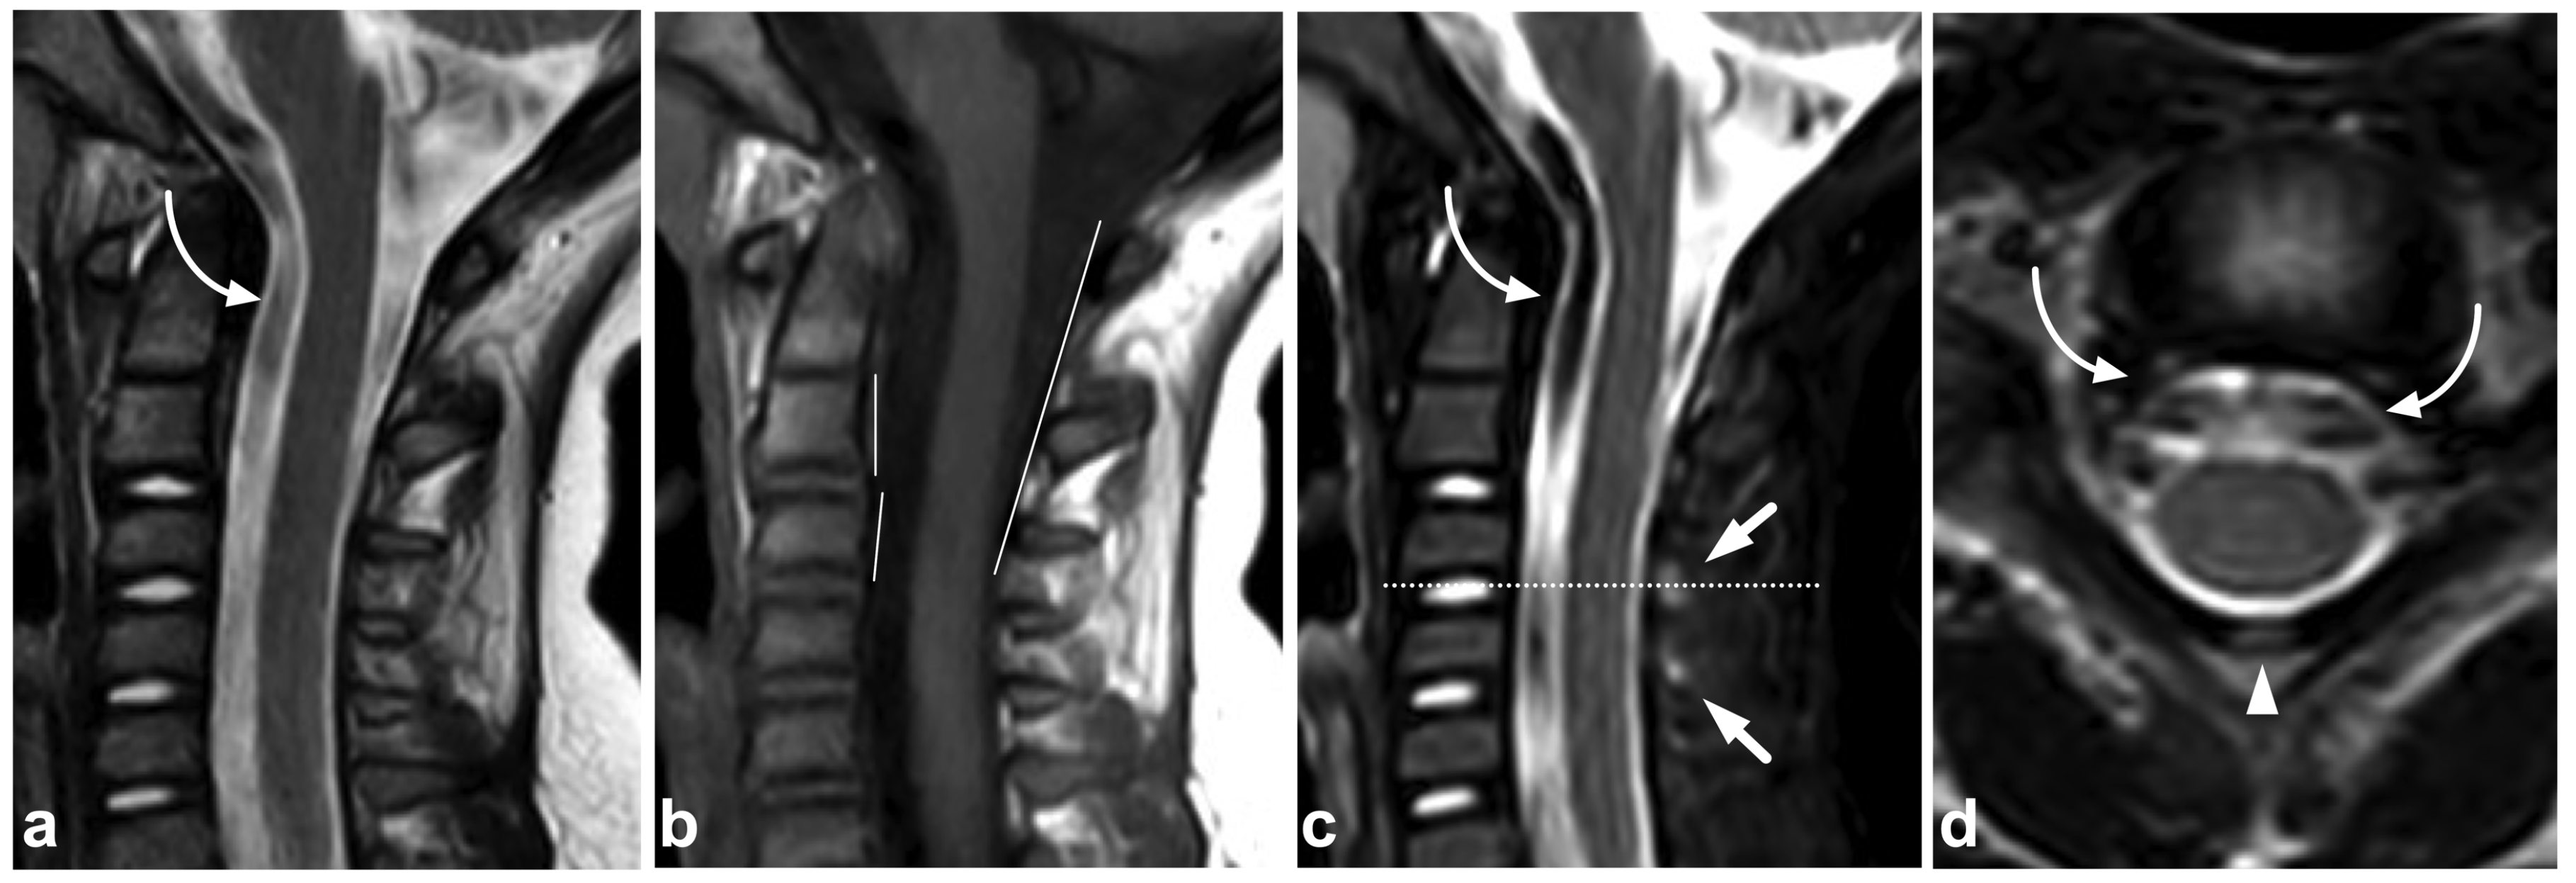

7.1. Pseudosubluxation of the Cervical Spine

7.2. Vertebral Wedging